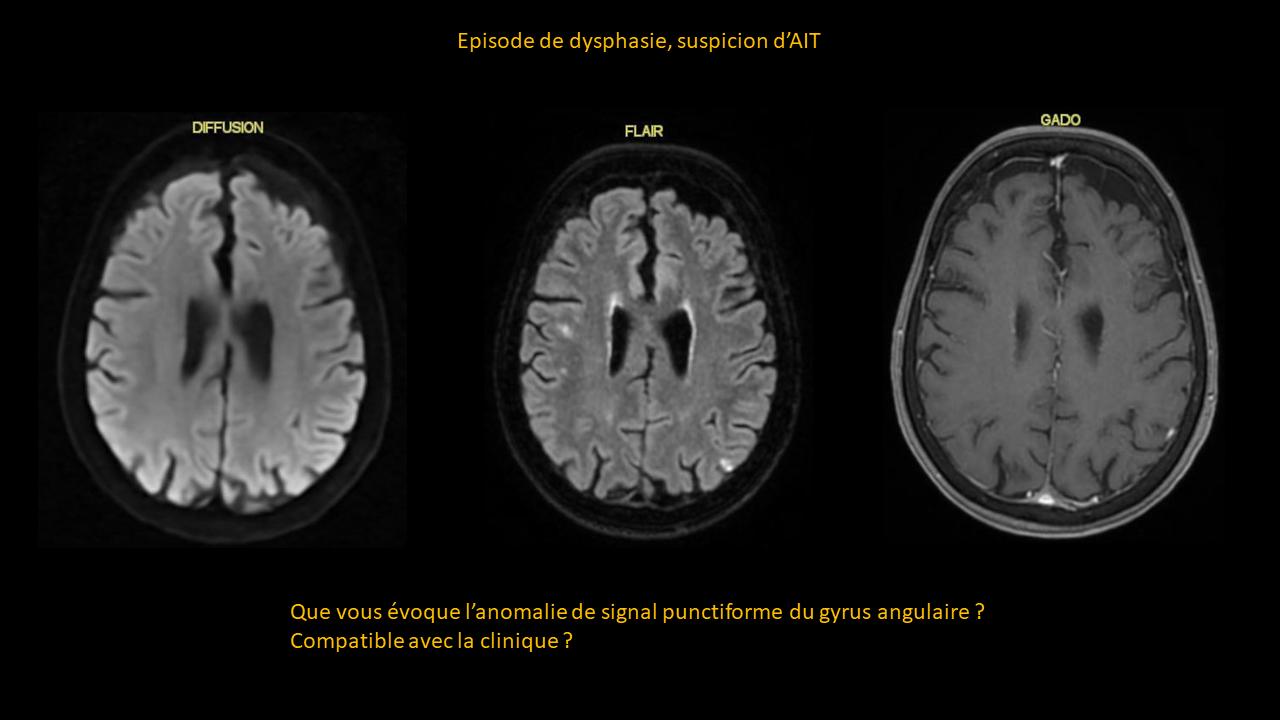

Système nerveux central